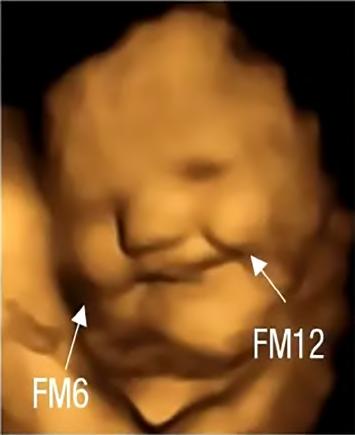

Si el sabor de la col rizada te hace fruncir elceño,noestássola.Loscientíficoshan descubierto que los fetos en el útero parecen sonreír después de que sus madres comen zanahorias y fruncen el ceñodespuésdequecomanesacol El Laboratorio de Investigación Fetal y Neonatal de la Universidad de Durham, en Reino Unido, afirma que es la primera evidencia directa que muestra fetos respondiendo a diferentes sabores en tiemporeal.Losinvestigadoresestudiarona unas 100 mujeres embarazadas y a sus bebéspornacerenInglaterra.Lesdierona 35 mujeres cápsulas que contenían zanahorias en polvo y a otras 34 embarazadas col rizada en polvo. Las 30 mujeres restantes formaron parte de un grupodecontrolynoconsumieronninguno delosdos.Enelestudioquepublicaronen la revista Psychological Science, el grupo informóque20minutosdespuésdequelas madrestragaranlascápsulaslasecografías

"Sabemos por investigaciones anteriores que la nutrición que reciben los fetos a travésdeladietadelamadreesrealmente importante para un desarrollo saludable posterior. Pero lo que no sabemos es cuándo comienza realmente (a sentir estos sabores)", dice Nadja Reissland, coautora del estudio y directora del Laboratorio de Investigación Fetal y Neonatal de la Universidad de Durham. "Los bebés por nacermuestransupreferenciaporelazúcar a las 14 semanas de gestación". "Para nuestroexperimento,lesdimosalosbebés por nacer las cápsulas en polvo a las 32 y 36 semanas de gestación (el embarazo suele durar 40 semanas en total), ya que sus expresiones tienden a volverse cada vezmáscomplejas.

4D mostraron que la mayoría de los fetos expuestos a la col parecían hacer una mueca. Estudios anteriores han sugerido que nuestras preferencias alimentarias pueden comenzar antes del nacimiento, ya que el líquido amniótico que rodea al feto puede tener diferentes sabores, según la dieta de la mujer embarazada. Pero este nuevoestudiodelaUniversidaddeDurham afirma ser el primero en observar directamente la respuesta de los bebés por naceradiferentessabores.